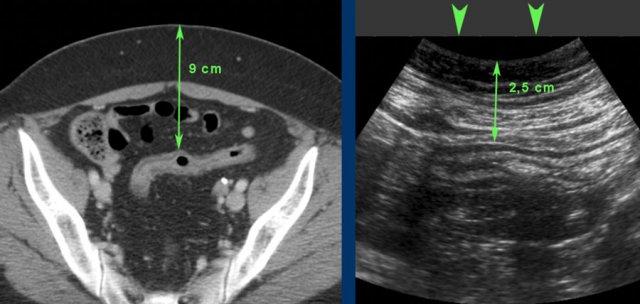

CT cho thấy đại tràng co thắt (mũi tên) ở bệnh nhân béo phì.

Khi ép nhẹ (ở giữa), đại tràng co thắt có thể được hiển thị bằng đầu dò 12 MHz.

Khi ép vừa phải (bên phải), đại tràng đã giãn ra thậm chí có thể được nhìn thấy bị dẹt áp vào cơ thắt lưng nằm ở phía sau.

CT của bệnh nhân béo phì bị viêm loét đại tràng không hoạt động. Đại tràng sigma nằm cách da 9 cm.

Trong quá trình ép (đầu mũi tên), khoảng cách này giảm xuống còn 2,5 cm, cho phép sử dụng đầu dò tần số cao.